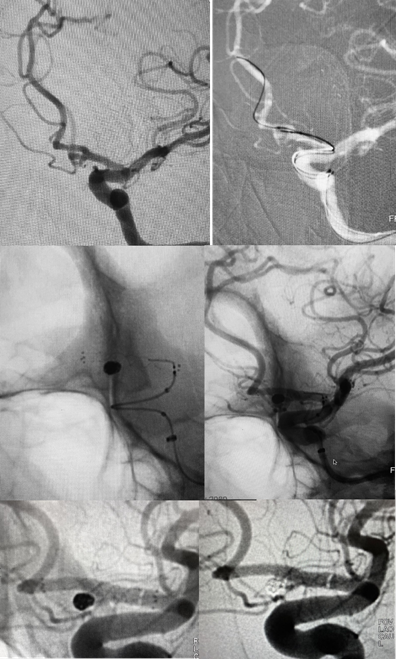

A 35-year-old previously healthy woman presented in emergency department complaining of severe headache, with a Grade 2 Hunt and Hess score. Neurological status was unremarkable. A computed tomography (CT) scan showed SAH (Modified Fisher Scale grade I) and the cerebrospinal fluid (CSF) sample showed 12.000 RBC/CC. Nevertheless, CT angiography did not depict any saccular aneurysm. Due to high suspicion, a three-dimensional rotational angiography was performed on day two, but showed only some minor AComA wall irregularities close to the left A1/A2 junction (Figure 1A). A second angiogram was performed 6 days later in order to elucidate the cause of the SAH and revealed a small pseudoaneurysm at this site (Figure 1B). Considering the acute morphological changes and the previous blending, we indicated urgent treatment. Microsurgical clipping occlusion of the AComA was discarded as an option since the lesion stretched out to the left A1/A2 segment. Since right A2 segment was supplied by right A1 segment, we decided to occlude AComA and the pseudoaneurysm with coiling and perform endovascular reconstruction of the left A1/A2 segments with a Flow Diverter Stent (FDS). The procedure was performed under general anesthesia and systemic heparinization (8000 IU during the procedure). The AComA occlusion was achieved with remodeling technique. A Scepter XC balloon 4 x 11m (Microvention Endovascular Inc., CA, USA) protected the left A1/A2 junction and three Microplex coils (Microvention Endovascular Inc., CA, USA) were detached through a Headway 17 microcatheter (Microvention Endovascular Inc., CA, USA). Finally, 2,5 x 14 x 20 mm Fred Jr Embolization Device (Microvention Endovascular Inc., CA, USA) (Figure 2) was placed through a Headway 21 microcatheter (Microvention Endovascular Inc., CA, USA), covering all the A1/A2 junction. Immediately after its placement, we administered intravenous abciximab 0.25 mg/kg bolus and maintenance dose for 12 hours. Dual antiplatelet therapy was initiated in the following day with clopidogrel 75 mg and aspirin 100 mg and kept for three months while aspirin was sustained for one year. External ventricular derivation was not required since there was no ventriculomegaly. Patient presented no evidence of new neurological deficits or complications such as rebleeding, regrowth, vasospasm, stent occlusion/stenosis or stroke. Control angiogram performed three months later confirmed exclusion of both pseudoaneurysm and the AComA (Figures 3) without any persistent arterial wall irregularity. Patient remained clinically stable with mRs 0.

Figure 1 On day one of hospitalization 3D angiography showed some minor irregularity of the AComA close to the left A1/A2 junction (arrow) (A and B). At day 7, 3D angiography revealed an pseudoaneurysm on the AComA (double arrow) with arterial wall irregularities on the AComA and on the left A1/A2 junction (C and D)..